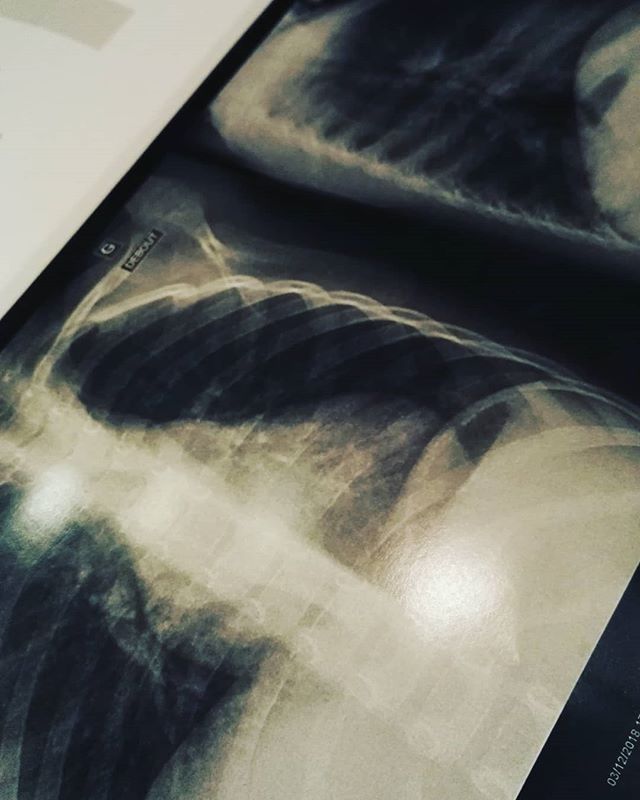

par Adeline3 décembre 201823 décembre 2018Laisser un commentaire sur Une pneumopathie pour Léandre ? Et donc une pneumopathie pour Léandre… Et donc 7jours d’antibios… Alors que ça fait 15jours que ça traîne… J’ai un peu les boules !!! ? Similaire Rédigé parAdelineRédactrice en chef, je suis la principale plume de ce blog !